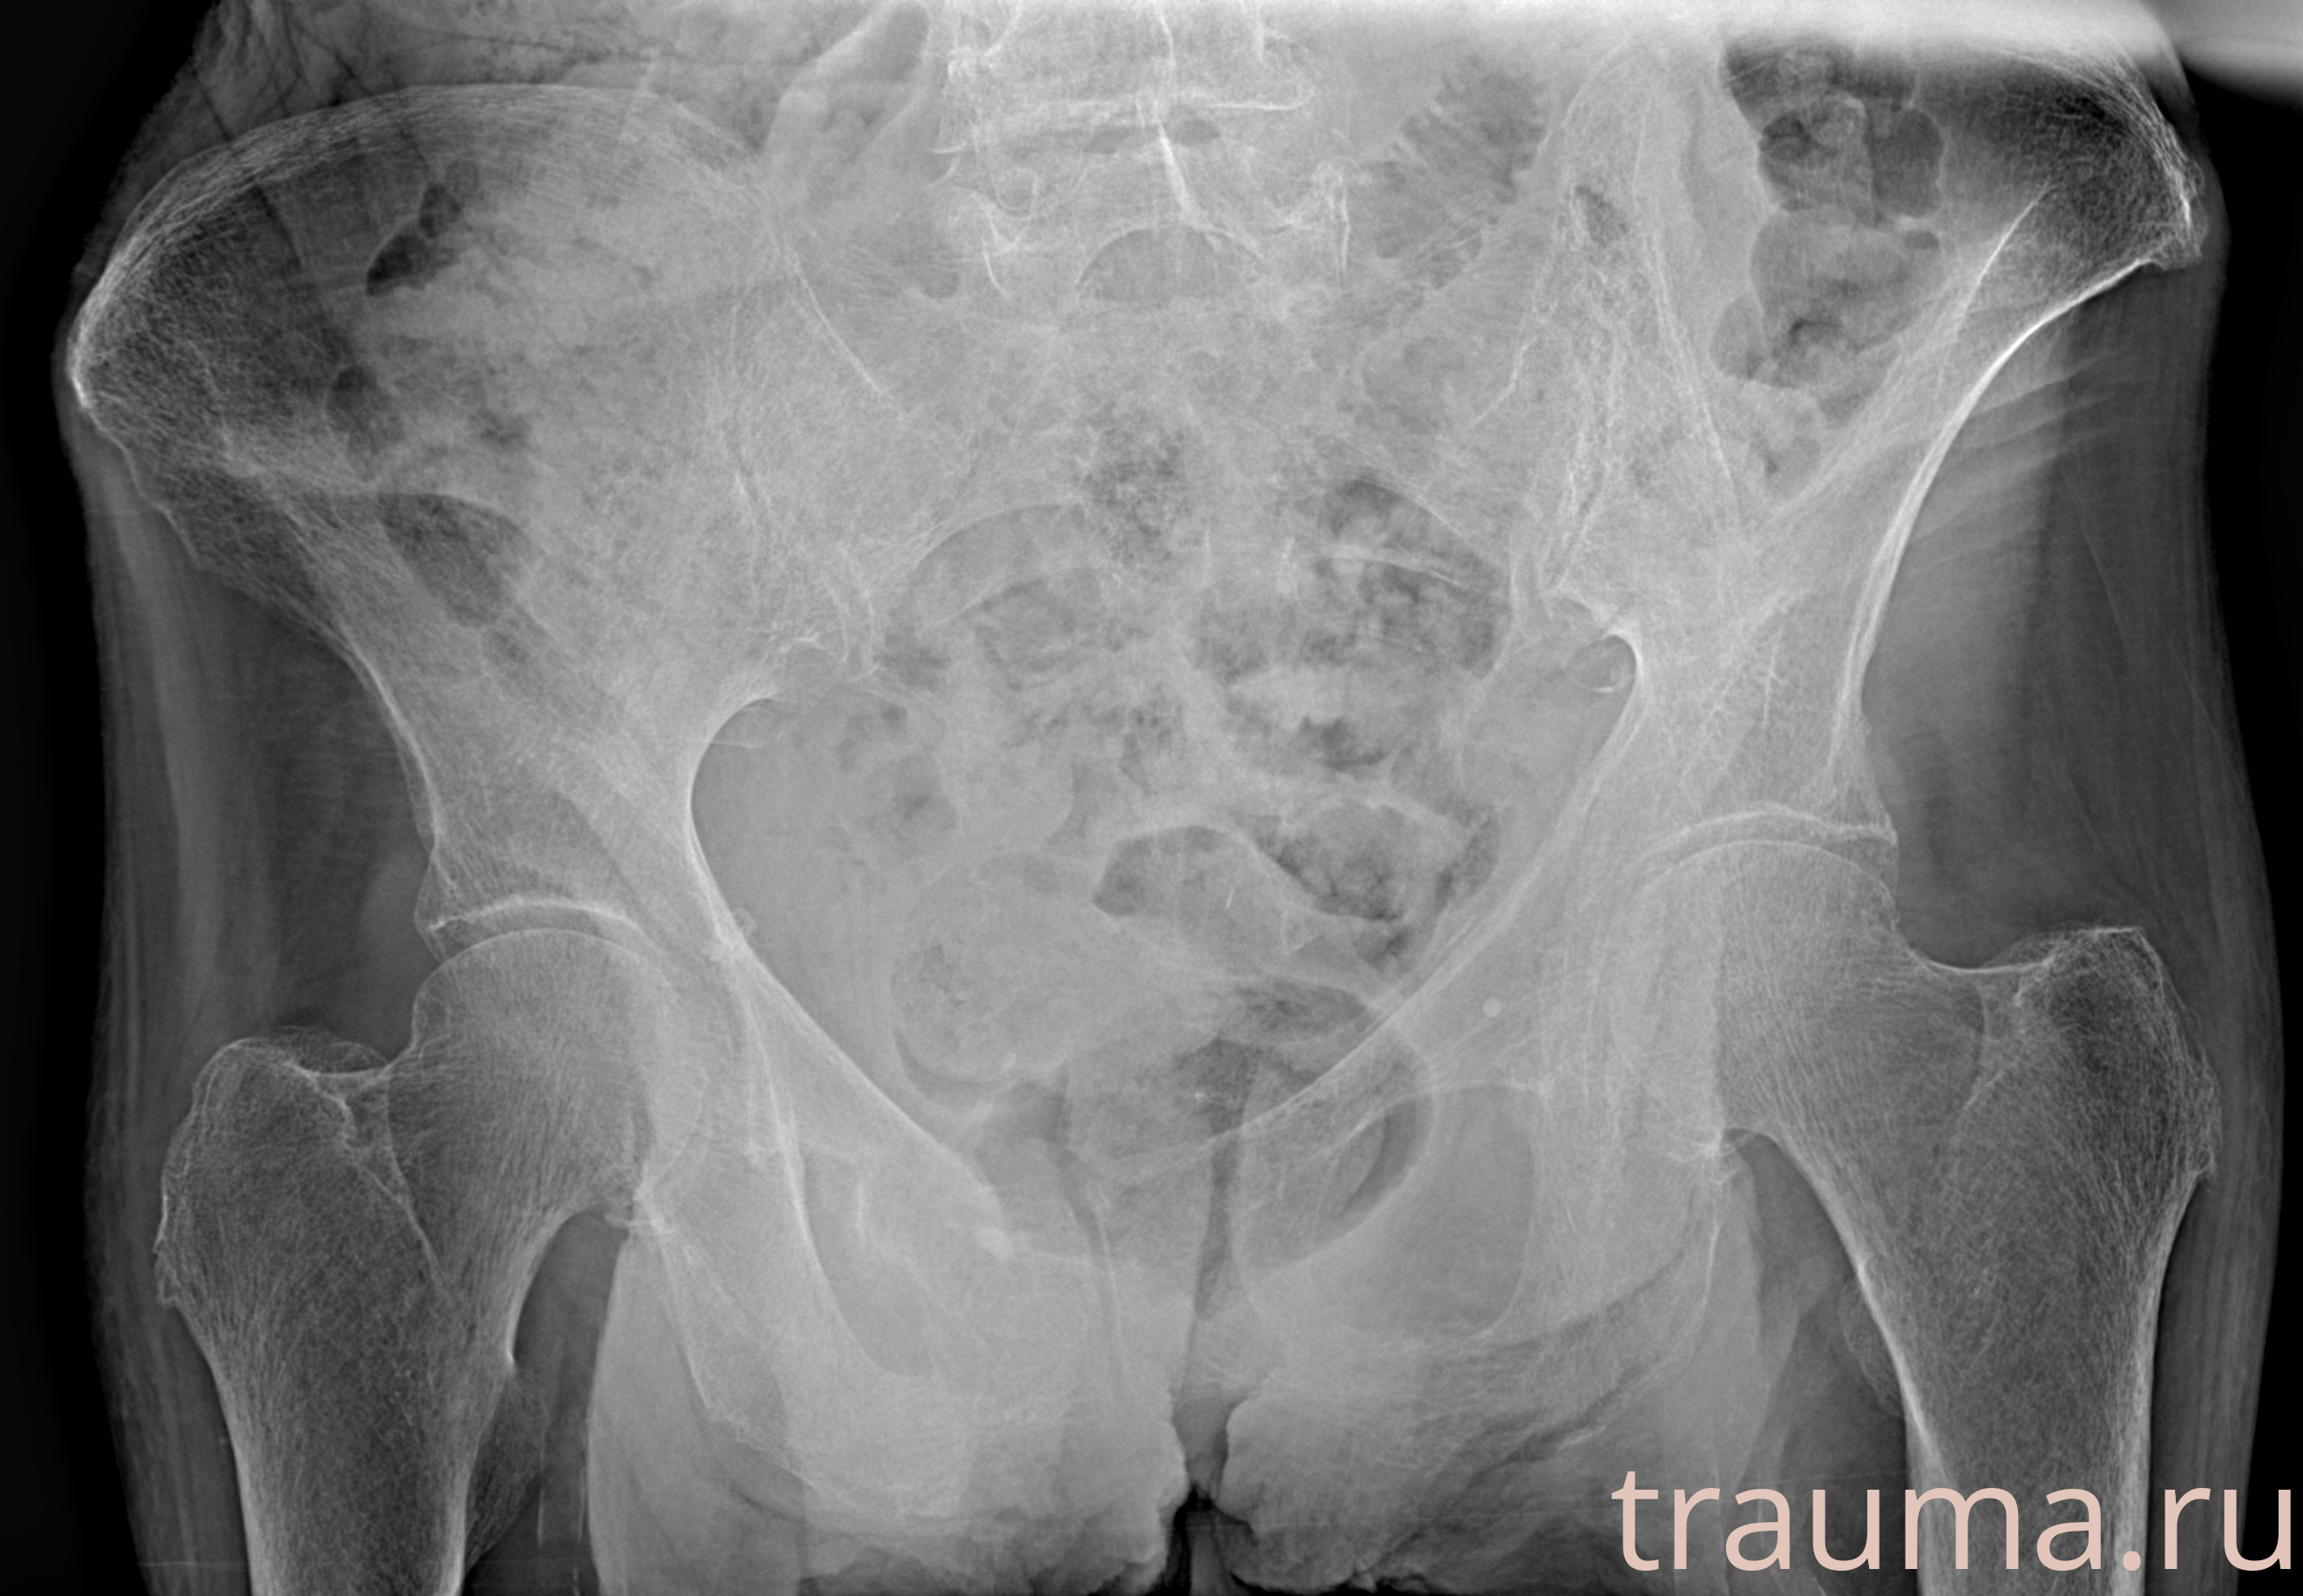

Рентген на дому: по вашему адресу приезжает врач-рентгенолог, травматолог-ортопед с мобильным рентгеновским аппаратом, проводит диагностику травмы или заболевания, делает необходимые рентгенограммы, дает рекомендации по дальнейшему лечению. Получить качественные снимки в домашних условиях возможно благодаря уникальной методике, разработанной МосРентген Центром для института  Склифосовского

при переломе шейки бедра и пневмонии от компании МосРентген Центр - партнера Института имени Склифосовского